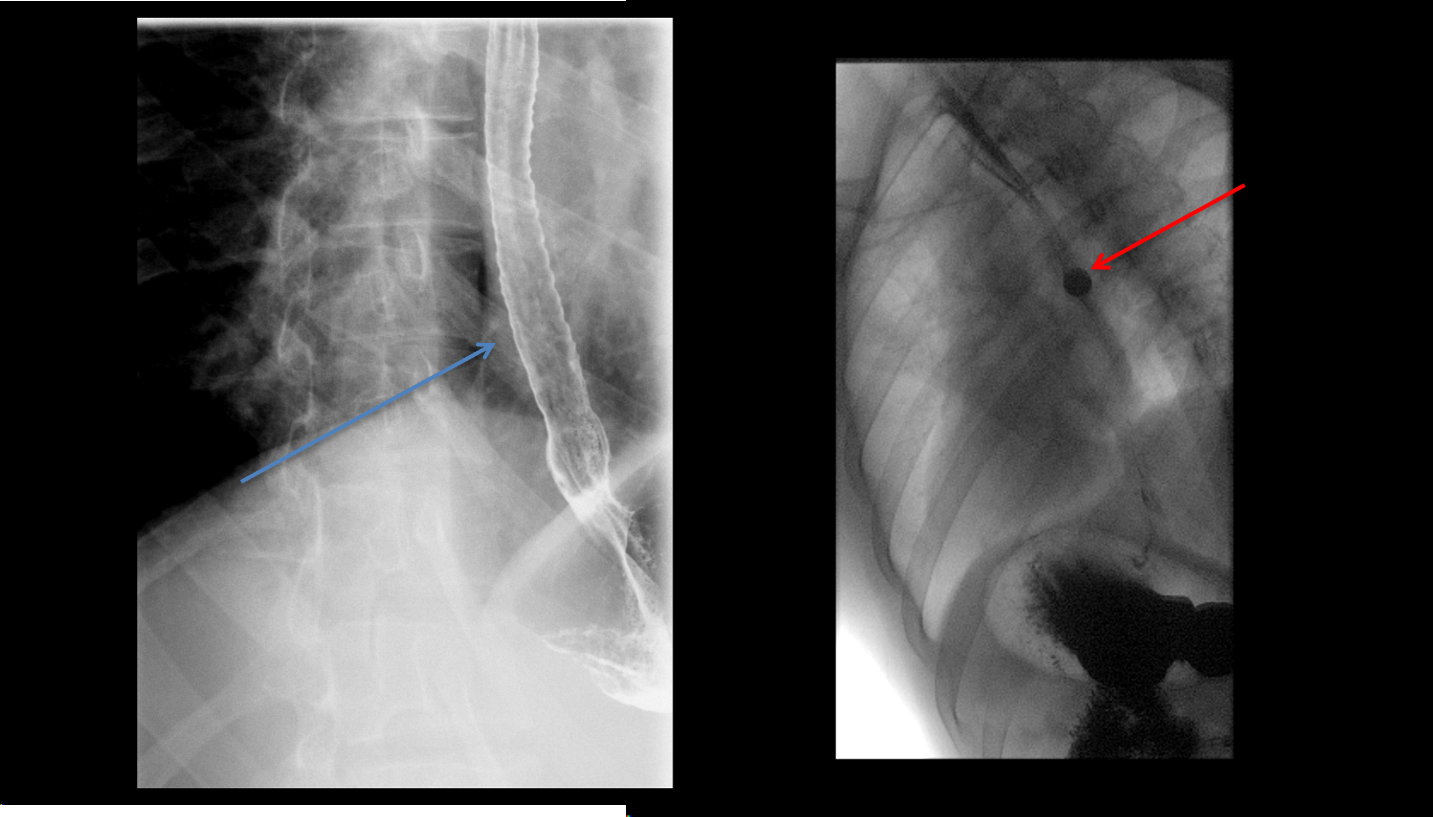

Esophagus with long segment narrowing, with corrugated appearance (blue arrow). 13 mm barium pill is unable to traverse the stricture (red arrow).